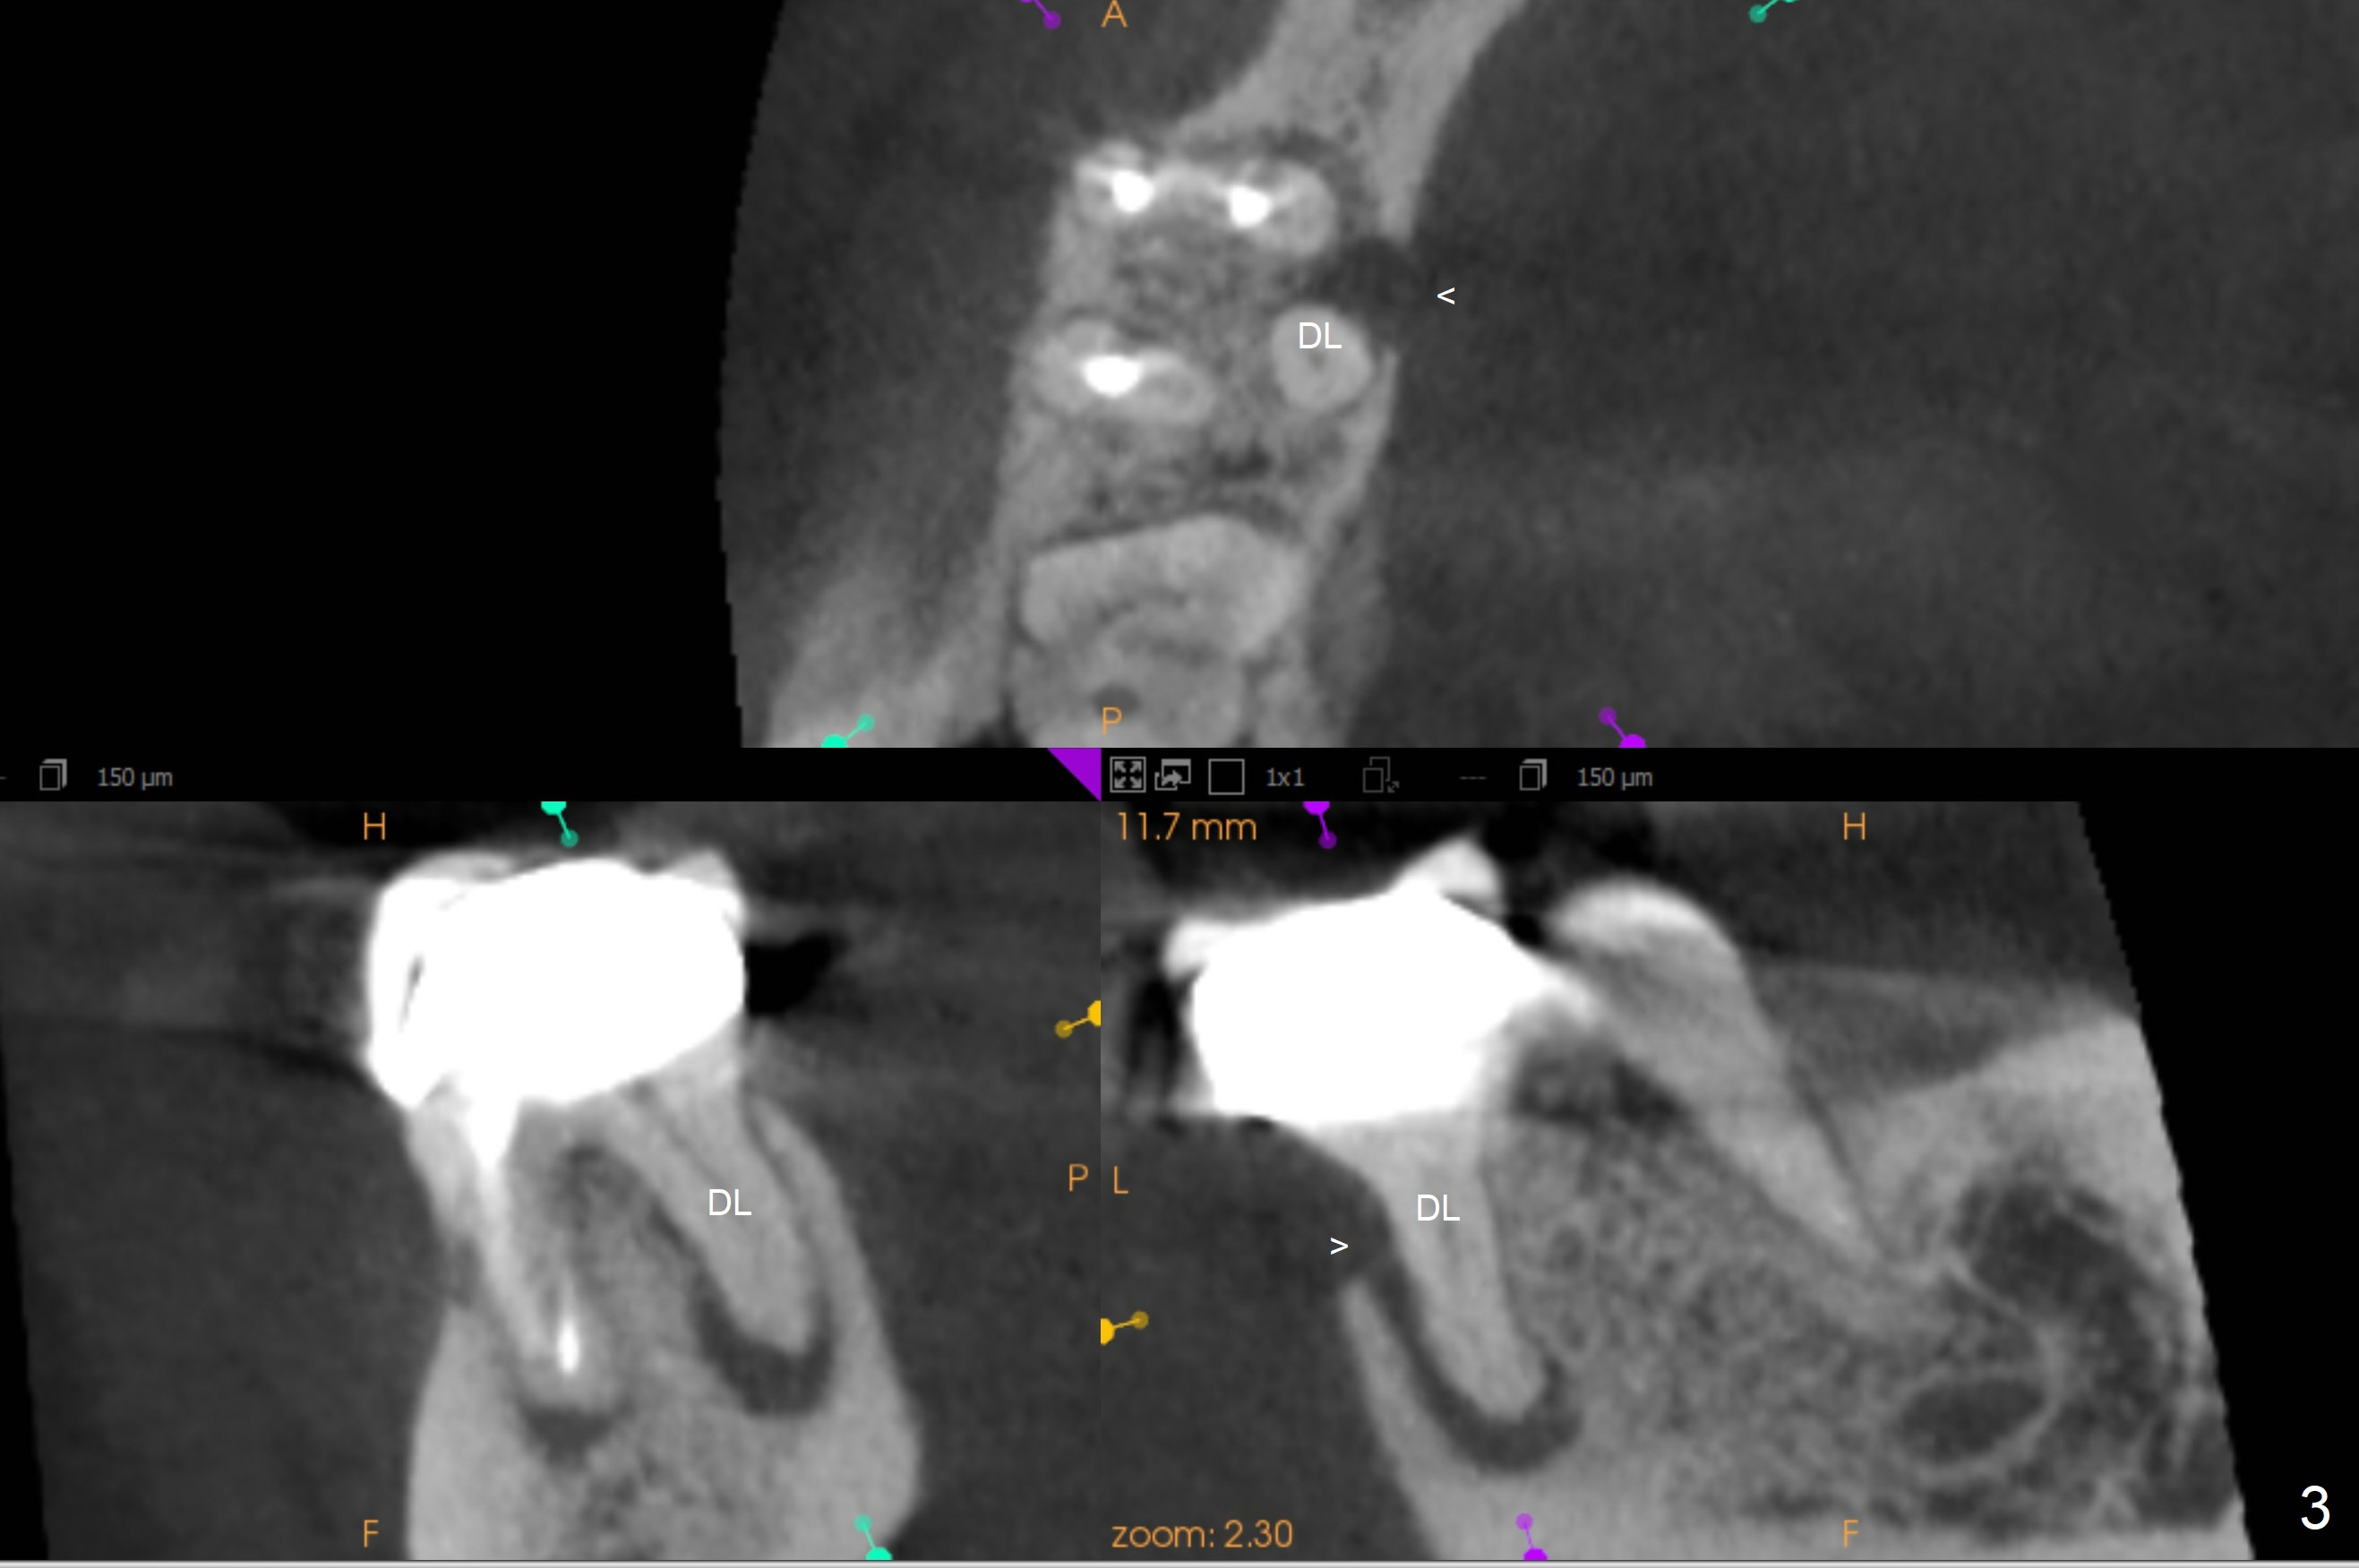

A 41-year-old slender woman returns for #29 and 30 implants (Fig.1,2) because of a fistula mesiolingual of #30 (Fig.3 arrowhead) several years post RCT. There is no deep pocket at #30. In fact the distolingual canal is missing (Fig.2 (black arrow),3 (DL)). RCT retreatment should solve apical periodontitis. Due to long term of missing #19 and 29, the mesiodistal space is limited with diastema between #28 and 29 (Fig.1, 2 (white arrowhead)). Limited ortho appears necessary prior to, during or post implantation. The ridge at #19 and 29 is not only narrow, but also short. It seems appropriate to place short 2- and 1-piece implants, respectively (Fig.5,4). As a matter of fact, there is open margin of the crown at #30 (data not shown). If the crown is to be removed prior to RCT, implantation is conducted before ortho, since the provisional can be made narrow mesiodistally.